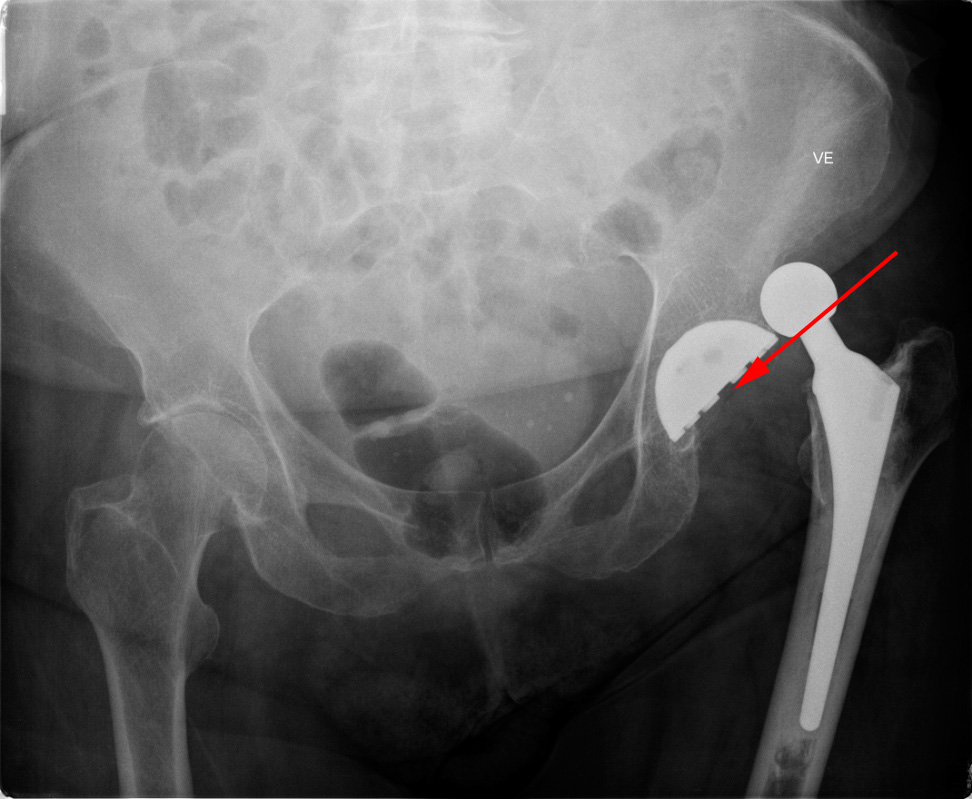

Røntgenundersøgelse af bækkenet viser en hofteprotese (rød pil), som er ude af led (hofteluksation).